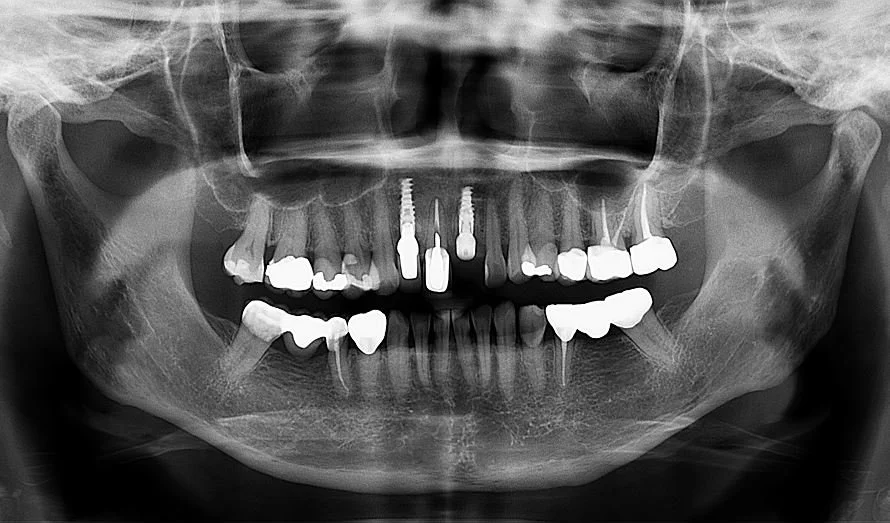

Digital x-rays are an advanced way of taking pictures of your mouth at the dental office. Evaluating the status of your dental implants, teeth, and surrounding bone is only possible with periodic x-rays. Compared to traditional film x-rays, the digital format uses lower dose of radiation, and are faster, safer, and more comfortable. Ensuring the bone and foundation for your smile is stable is an essential first step before any reconstruction can be started.

Thorough clinical and radiographic planning is important for creating a comprehensive treatment plan. The first step is to gently remove the diseased tooth and any surrounding infection without injuring the adjacent structures. With the proper use of dental anesthetic and careful instrumentation, this process is painless.

A detailed image taken using Cone-Beam Computed Tomography (CBCT), can reveal additional three-dimensional information about the tooth and surrounding structures. If certain conditions exist such as the absence of infection and bone loss, then a dental implant may be placed immediately after the tooth is extracted. This is known as an immediate implant placement.